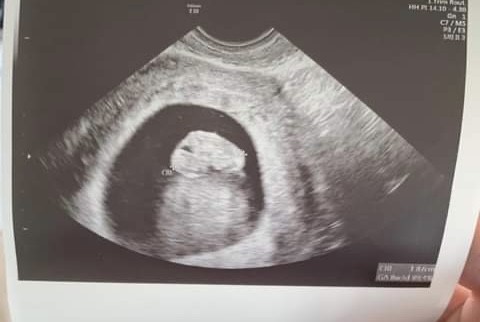

Skulone dziecko na usg

Hej, byłam wczoraj na usg i Pani doktor powiedziała, że dziecko jest BARDZO skulone, zestresowalo mnie trochę to, czy to źle że jest tak skulone, co to oznacza? Jak zapytałam czy wszystko jest dobrze z ciąża powiedziała że wszystko jest okej. Ogólnie ja od początku ciąży mam bóle w podbrzuszu czasem lekkie czasem mocne, ale od początku mówią że wszystko z dzieckiem jest okej. Czy któraś z was miała taka sytuację? Trochę mnie martwi, że dziecko było tak bardzo skulone.

U mnie tez jest skulony, lekarka mówiła ze po prostu tak się dziecko ułożyło, wiec chyba nie ma czym się przejmować:)

• C29DBD87-EDF2-4F06-A9F2-3A49ADD67524.jpeg